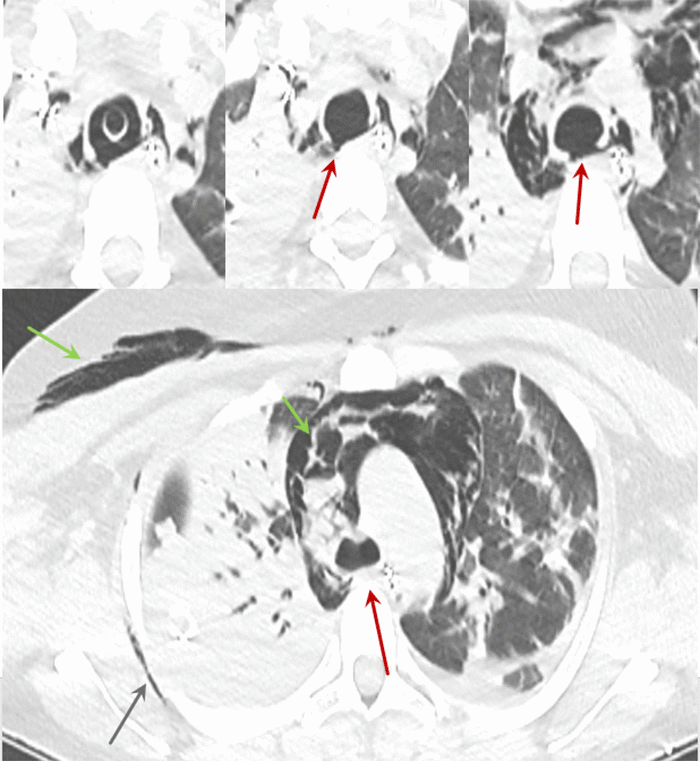

On arrival, the patient remained hypoxic and difficult to ventilate. Bronchoscopy was repeated, which showed a partially collapsed trachea with suspicion for a poorly visualized posterior tracheal injury. CT was obtained, which showed extensive pneumomediastinum, pneumothoraces, subcutaneous emphysema, and a defect in the posterior trachea (Figure 1). The position of the defect was consistent with a likely source for the bilateral pneumothoraces and pneumomediastinum. Thoracic surgery was consulted for evaluation for repair, which they felt would be possible if the patient could be stabilized. VV ECMO was initiated for hypoxia and failure to ventilate adequately. Right 21Fr internal jugular and left 25Fr femoral catheters were placed. Initial settings included a flow of 4.9L/min, 3600 RPM, sweep gas flow of 6L/min, and sweep gas FiO2 100%. The patient was successfully oxygenated with oxygen saturations greater than 88%. To avoid further airway trauma, she was sedated to prevent respiration, and ventilation was discontinued.

Figure 1. Initial Imaging. Published with Permission

Top: Sequential axial images in lung windows show that immediately inferior to the ET tube, there is apparent discontinuity of the posterior trachea (red). Bottom: Origin of the mainstem bronchi appears intact (red). Mediastinal and soft tissue emphysema (green) are noted as well as atelectasis (blue).